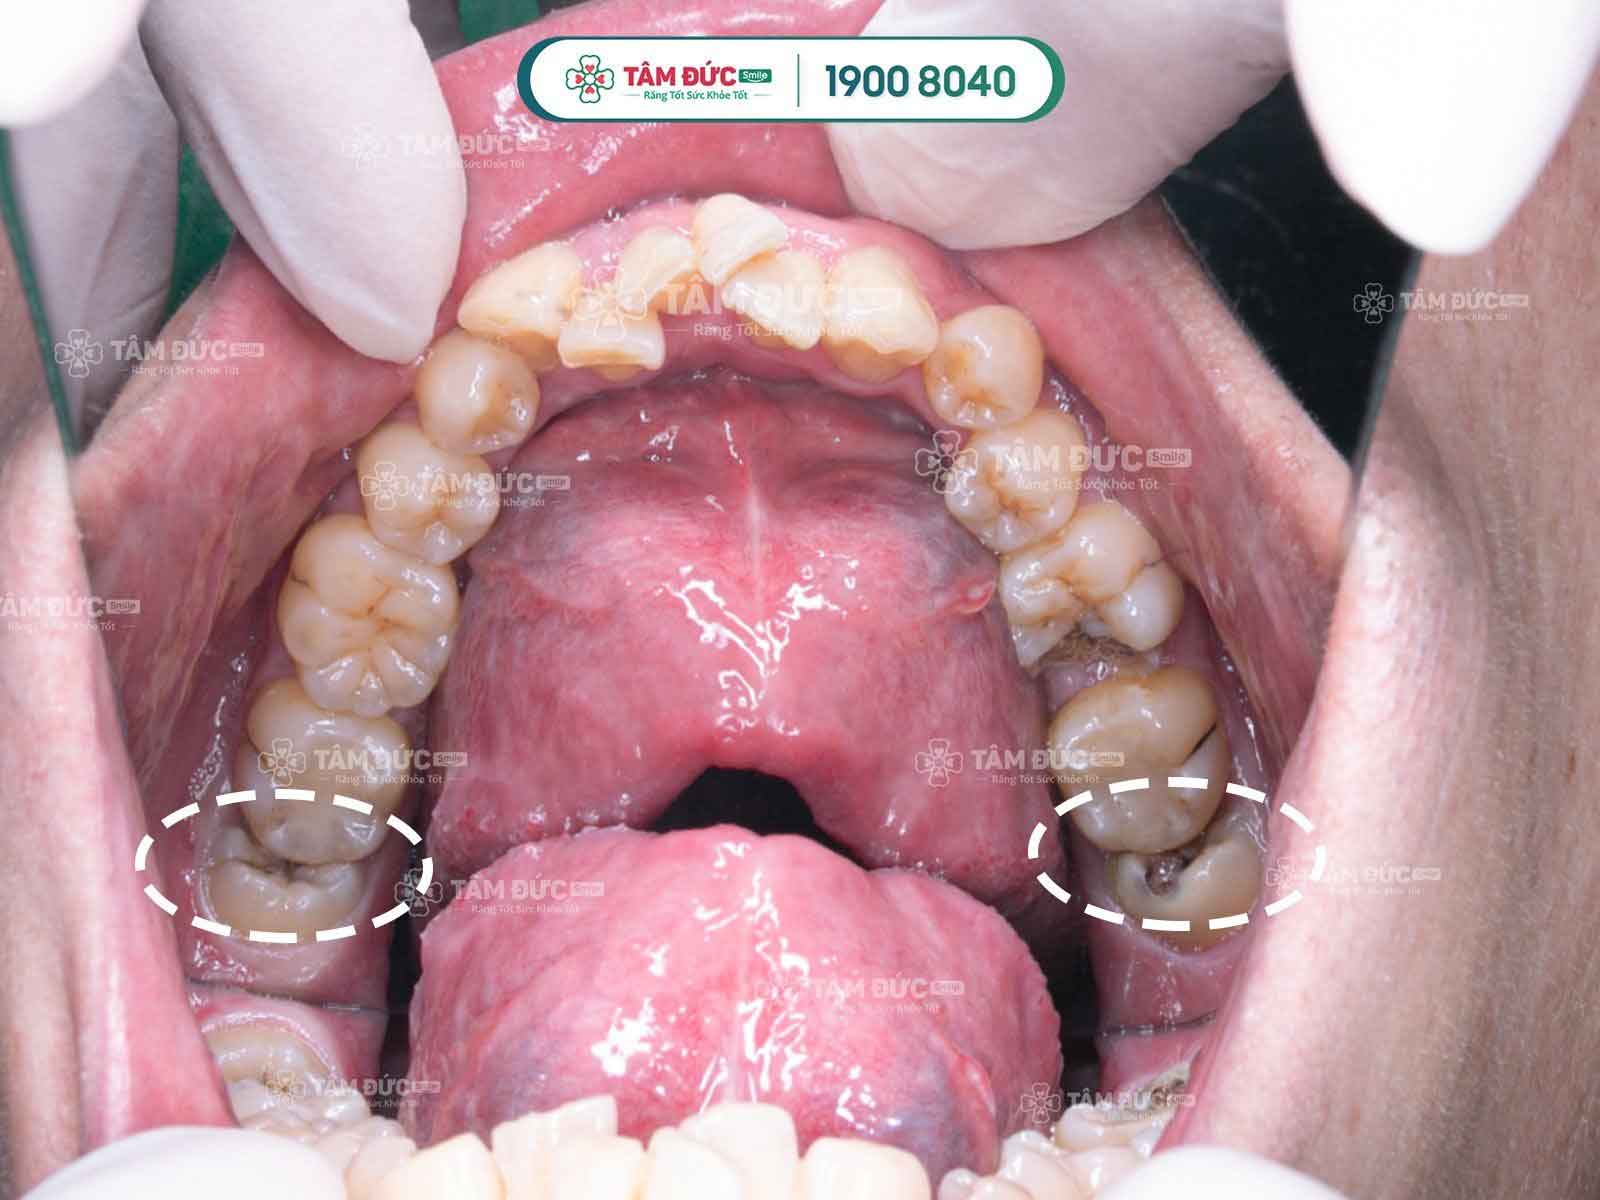

Răng khôn mọc lệch gây đau nhức